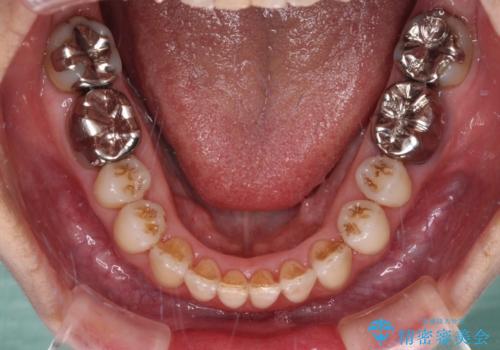

上顎骨の幅が下顎骨よりも小さいので、拡大装置により骨幅を広げて上下関係を改善すると同時にワイヤー矯正で反対咬合の改善を図り、その後インビザラインにて歯並びを整えることとしました。

急速拡大装置の使用により奥歯の咬み合わせが劇的に変わり、その変化を利用して反対咬合を改善することができました。

治療期間中は奥歯が咬み合わず、食事が取りにくいなどの不都合がありましたが、最終的にはきれいに整えることができました。